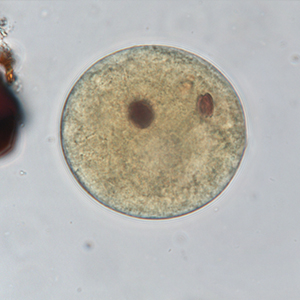

Le kyste est sphérique à ovoïde, à paroi épaisse, mesurant 50 à 100 μm de diamètre. Il présente un contenu granuleux, un macronucléus et micronucléus difficilement visibles (Strait et al., 2012). La coloration au Lugol permet de mettre en évidence certains organites qui apparaissent en brun sombre, de colorer la paroi en brun et l’intérieur du kyste en jaune.